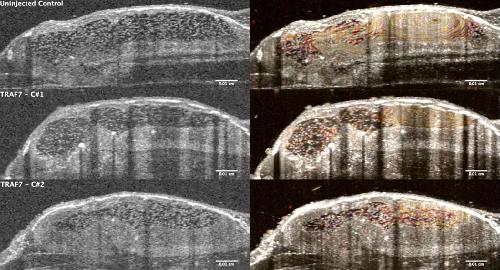

Pleiotropic role of TRAF7 in skull-base meningiomas and congenital heart disease., Proc Natl Acad Sci U S A 2023 |